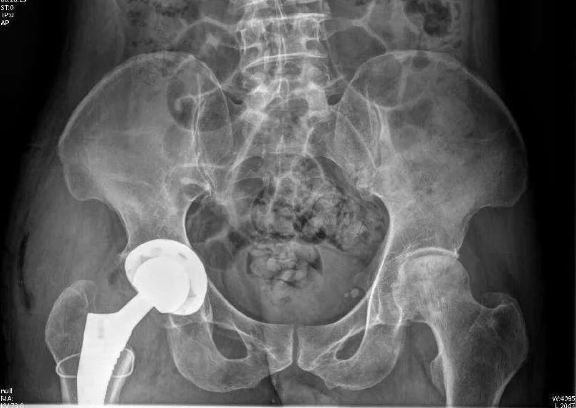

韩主任向周先生及家属说明治疗方案,他们表示理解也积极支持手术。完善术前准备后,韩主任手术团队为周先生行右侧人工全髋关节置换术。手术耗时约2个小时,术中截除坏死的股骨头并植入髋关节假体后,髋关节被动活动良好,手术顺利完成。

术后第二天复查,假体位置良好

术后第二天,周先生感觉良好,已经开始在康复师指导下,进行卧床屈伸功能康复锻炼了。